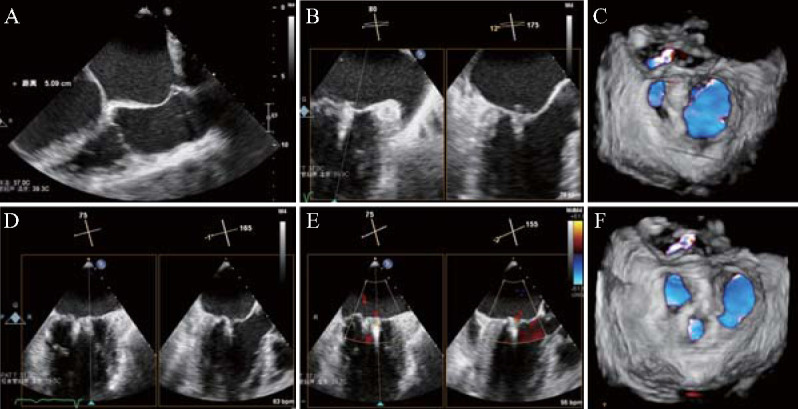

A 91-year-old male patient was admitted with a history of mitral valve prolapse diagnosed by physical examination ten years prior and recent onset of exertional chest discomfort persisting for over one month. Transthoracic echocardiography showed that the anterior leaflet of mitral valve was thickened and prolapsed with severe regurgitation, and transesophageal echocardiography further confirmed that the anterior and posterior leaflets of mitral valve were prolapsed with massive regurgitation (A1, A2, A3, P1 and P2 were all prolapsed). Thus, the diagnosis of Barlow syndrome was considered. Transcatheter edge-to-edge mitral repair was performed with two MitraClipTM G4 XTWs. After a 10 months follow-up, the patient's cardiac function was significantly improved, and the degree of mitral regurgitation was mild.

患者男,91岁,疑有Barlow病病史,体检诊断为二尖瓣脱垂10余年,运动后胸闷1个多月。经胸超声心动图显示二尖瓣前小叶增厚脱垂伴严重反流,经食管超声心动图进一步证实二尖瓣前、后小叶脱垂伴大量反流(A1、A2、A3、P1、P2均脱垂)。经导管二尖瓣边缘到边缘修复用两个Mitraclip XTWs。随访3个月,患者心功能明显改善,二尖瓣返流程度轻度。